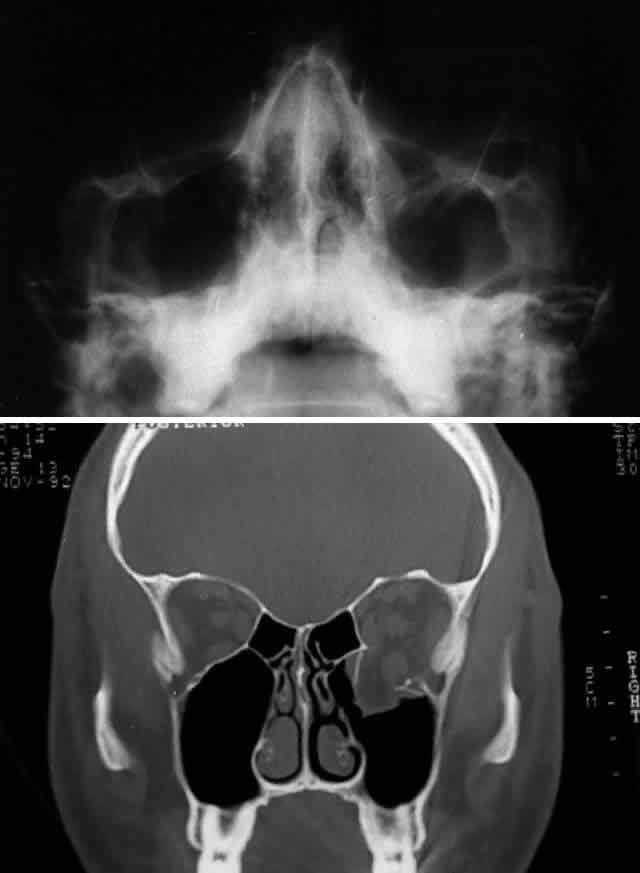

RADIOLOGIC IMAGING

After the history and physical examination, consideration is given to further assessment of the orbital injury with radiologic imaging. The indications for radiologic imaging area are based on the physician's assessment of the injury and include gross orbital and facial deformity, limitation of ocular motility, and associated neurologic injuries. CT is the imaging modality of choice in the assessment of orbital/craniofacial fractures because it provides excellent detail of the bony injury as well as the orbital soft tissues in most cases (Fig. 4). Ideally, both axial and direct coronal views are preferred. Coronal views are necessary for adequate imaging of the orbital floor and orbital roof. With direct views, 3-mm views (cuts) are usually adequate. In cases in which the patients cannot be positioned for direct coronal imaging, coronal reconstructions can be performed, provided that finer (1.5-mm) axial cuts are used. Reconstructed coronal images lack the resolution of direct coronal images, but they are usually adequate when direct coronal imaging cannot be obtained. Spiral CT, which allows rapid imaging and multiplanar formatting, will likely become useful in the assessment of orbital trauma as this newer technology becomes increasingly available.

Craniofacial fractures can also be imaged with the use of three-dimensional (or, more accurately, pseudo-three-dimensional) reconstructions. Although three-dimensional reconstructions can provide a perspective that may help conceptualize the extent of the injury, they are not essential for treatment. Three-dimensional imaging has some disadvantages: besides entailing additional cost, time, and radiation, it obscures the intricate details of fracture anatomy in the middle orbit by summing individual images. This technique also provides no information regarding the relationship between bone and soft tissues, which is particularly important in the assessment of orbital injuries. Standard two-dimensional CT scans, however, adequately show the degree of orbital bony disruption as well as the associated orbital soft tissue changes, particularly the relationship of the extraocular muscles (and orbital connective tissues) with the fracture site.1

Before CT scanning was readily available, facial x-ray series were used in the radiologic assessment of orbital fractures. Typical views included Caldwell's (anteroposterior) view, Waters' view, lateral view, and submental vertex view (particularly good for viewing the zygomatic arches). Waters' view, which is obtained with the chin slightly elevated, is considered the most useful x-ray view for imaging the orbital floor, inferior rim, and maxillary sinus. Because CT scans are superior to x-rays in terms of sensitivity and reliability, in most situations today plain orbital/facial x-rays are obtained only when a CT scan is unavailable or when only very minimal injury is suspected. Magnetic resonance imaging (MRI), although able to image orbital soft tissue exquisitely well with a small surface coil, is generally of limited usefulness in the initial assessment of orbital/craniofacial injuries because of its limited ability to image bone. It is contraindicated in cases of suspected retained ferromagnetic foreign bodies. MRI may have a secondary role in the management of orbital trauma in cases where CT scanning suggests the presence of soft tissue injury, such as intramuscular hemorrhage or sub-dural optic nerve sheath hemorrhage. In such cases, the better soft tissue resolution potentially available with MRI may allow more specific diagnostic interpretation.2